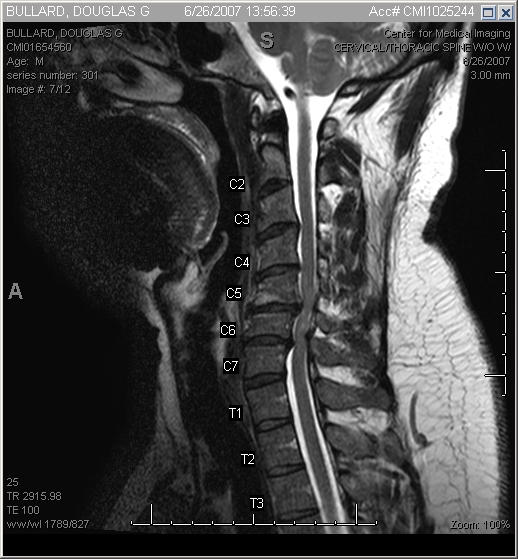

I got the CD of the MRI at the imaging facility, got home, and popped it into my PC. As soon as I pulled it up, I knew something was wrong. My spinal cord was obviously being pinched in several places by extruded cervical discs (see preoperative pics below).

MRI of the cervical spine. Notice the bulges in the discs pressing on the spinal cord between vertebrae C5-C6 and C6-C7. Also note the whitish areas in the spinal cord where it’s compressed.